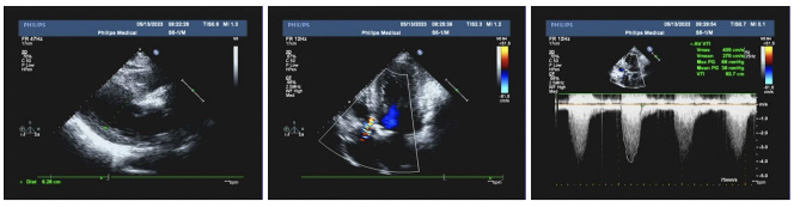

患者主動脈瓣口面積小,鈣化嚴重,為手術帶來了很大困難,術者小心翼翼地將導絲送入患處,跨瓣、瓣膜定位、釋放球囊……凌晨4:20,隨著大鞘的退出,標志著一場與死神賽跑以勝利謝幕。在多學科緊密協作下,急診TAVR手術圓滿成功,患者術后血流動力學指標即刻得到改善,跨瓣壓差從160mmHg下降到僅為5mmHg!復查心臟彩超提示主動脈瓣狹窄完全解除!患者各項生命征數值平穩,病情轉危為安!